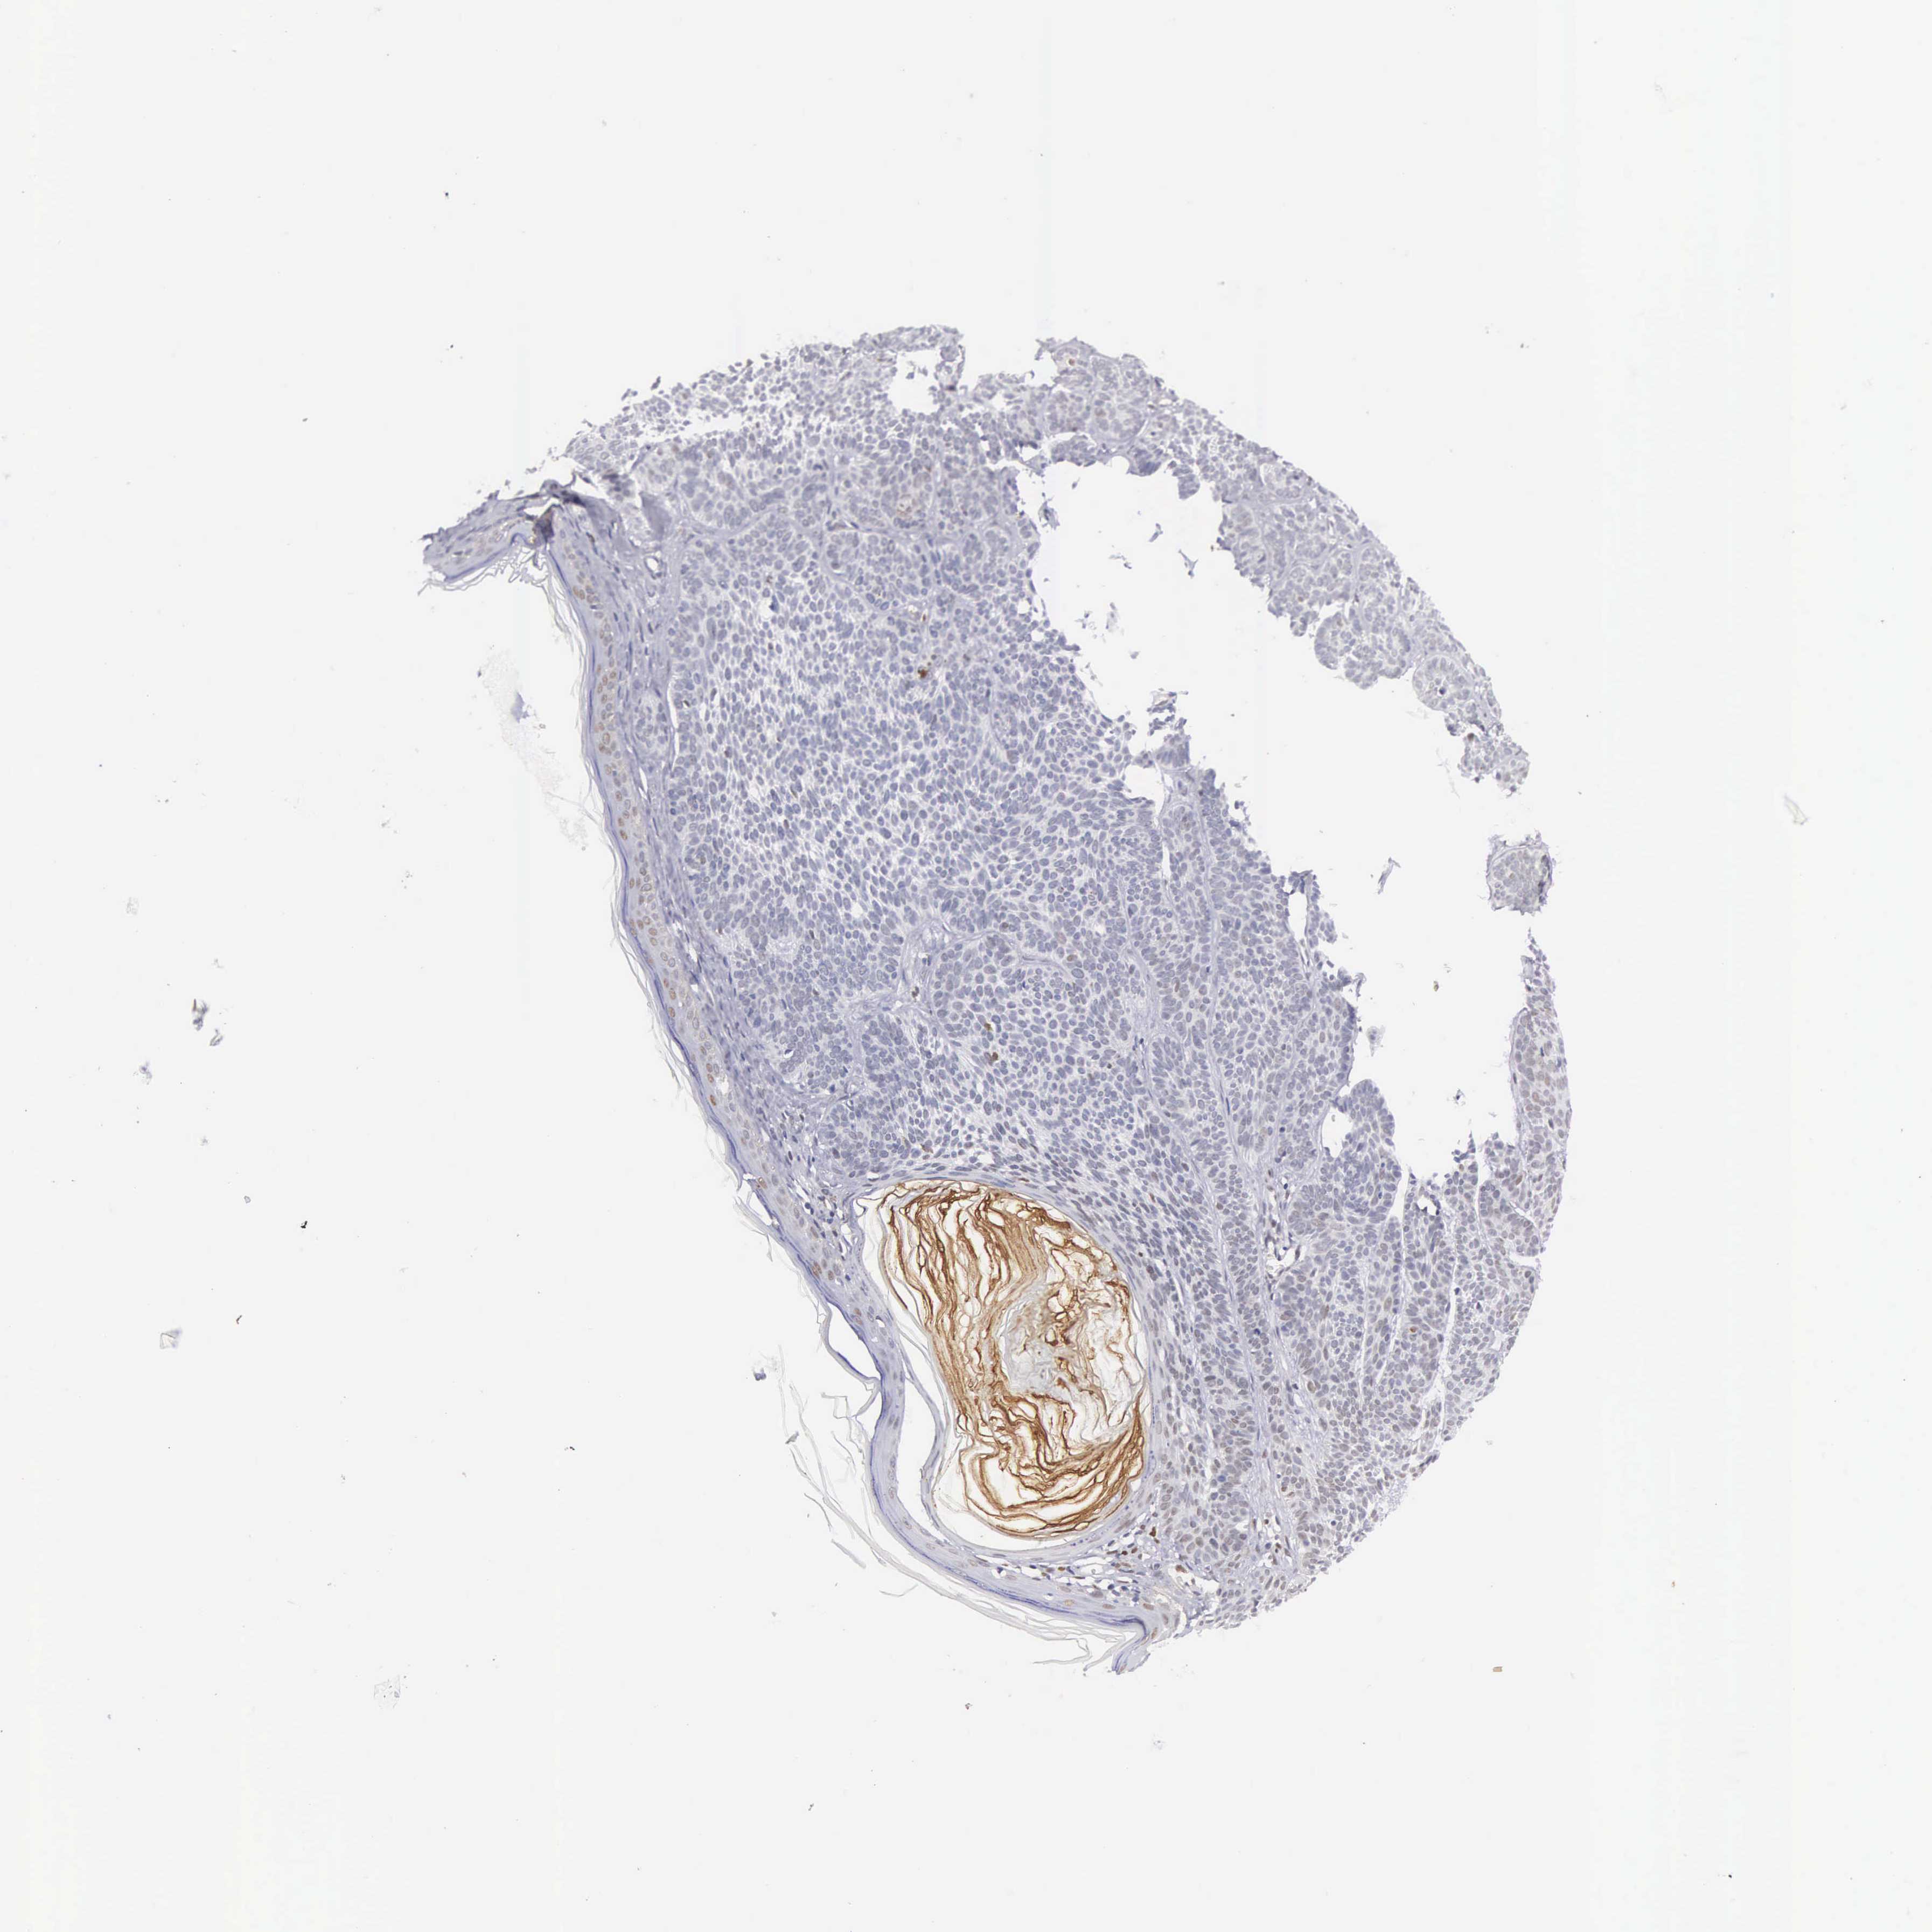

Basal cell and squamous cell cancer

SKIN CANCER - Protein expressioni

A mouse-over function shows sample information and annotation data. Click on an image to view it in a full screen mode. Samples can be filtered based on level of antibody staining by selecting one or several of the following categories: high, medium, low and not detected. The assay and annotation is described here.

Each image is clickable and will lead to virtual microscopy that enables deeper exploration of all samples and also displays staining intensity scores, fraction scores and subcellular localization as well as patient and tissue information for each sample.

Antibody HPA000264

Staining

High

Intensity

Strong

Quantity

>75%

Location

Nuclear

Squamous cell carcinoma, NOS

Basal cell carcinoma